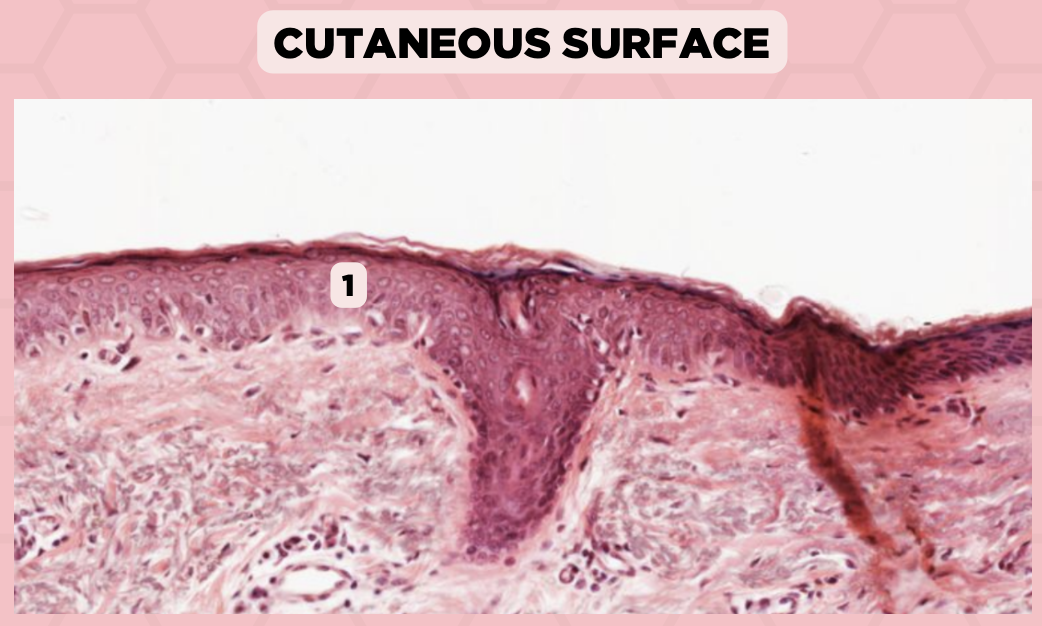

Lip

What specimen is being showed in this picture?

Keratinized Stratified Squamous Epithelium (Epidermis)

Identify the structure labeled as 1.

d. Mucosa/Mucous Membrane

Identify the structure labelled in the given image?

a. Epidermis

b. Dermis

c. Hypodermis

d. Mucosa/Mucous Membrane

b. Nonkeratinized stratified squamous epithelium

Identify the structure’s lining epithelium given in the image?

a. Keratinized stratified squamous epithelium

b. Nonkeratinized stratified squamous epithelium

Lip

What specimen is being showed in the picture?

Non-Keratinized Stratified Squamous Epithelium (Mucosa/Mucous Membrane)

Identify the structure labeled as 1.